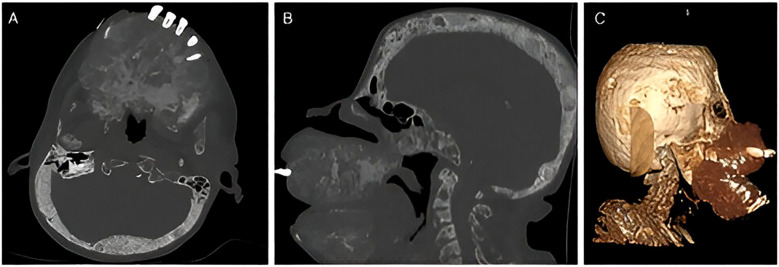

三期甲状旁腺功能亢进(THPT)是不受控制的继发性甲状旁腺功能亢进的严重并发症,通常与晚期慢性肾脏疾病(CKD)相关。我们报告了一名洪都拉斯患者的病例,她长期患有继发于严重子痫前期的CKD病史,由于经济拮据和COVID-19大流行,她在停止治疗后患上了THPT。患者表现出严重的颌面畸形、功能限制和广泛的骨骼异常。尽管最初使用了paricalcitol和alfacalcidol等药物进行治疗,但由于缺乏适当的治疗方法和计划中的甲状旁腺切除术的推迟,使她的病情恶化。该病例强调了早期诊断和及时干预的重要性,特别是在资源有限的情况下,强调了发展中国家迫切需要肾脏移植项目和改进预防策略。

Tertiary hyperparathyroidism (THPT) is a severe complication of uncontrolled secondary hyperparathyroidism, typically associated with advanced-stage chronic kidney disease (CKD). We present the case of a Honduran patient with a long-standing history of CKD secondary to severe preeclampsia, who developed THPT following the discontinuation of her treatment due to financial constraints and the COVID-19 pandemic. The patient exhibited severe maxillofacial deformities, functional limitations, and widespread skeletal abnormalities. Despite initial management with medications such as paricalcitol and alfacalcidol, the lack of access to appropriate therapies and the postponement of a planned parathyroidectomy worsened her condition. This case highlights the importance of early diagnosis and timely intervention, particularly in resource-limited settings, emphasizing the urgent need for kidney transplant programs and improved preventive strategies in developing countries.